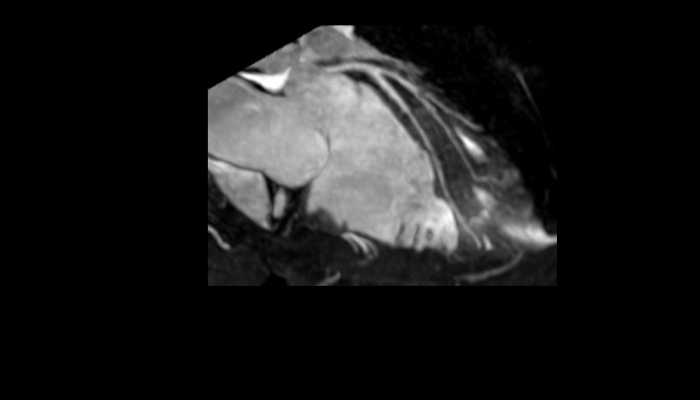

頭部MRI画像 頭部MRI脳腫瘍や脳梗塞、認知症など脳の病気を詳細に評価します。 MRA画像 頭部MRA造影剤を使わずに脳の動脈を描出します。動脈瘤や狭窄を検索します。 脊椎MRI画像 脊椎MRI椎間板ヘルニアや脊柱管狭窄症など脊椎や脊髄の疾患を評価します。 腹部MRI画像 上腹部MRI・MRCP肝臓・胆のう・膵臓・腎臓などの上腹部の重要臓器を詳細に評価します。 乳房MRI画像 乳腺MRIマンモグラフィや超音波と併せて、乳がんを検索や病変の範囲を評価します。 前立腺MRI画像 前立腺MRI前立腺がんを検索します。PSA高値の方はまず前立腺MRIをお勧めします。 子宮・卵巣MRI画像 子宮・卵巣子宮筋腫や子宮体癌、卵巣腫瘍など女性特有の病気を評価します。 膝関節MRI画像 膝関節膝関節の骨や靭帯、半月板を評価します。靭帯断裂や半月板損傷などレントゲンでは評価できない構造も診断できます。 肩関節MRI画像 肩関節肩関節の骨や腱、靭帯を評価します。腱板断裂や腱の断裂などレントゲンでは評価できない構造も診断できます。 心臓MRA 心臓MRA狭心症、心筋梗塞の原因となる冠動脈の狭窄を評価します。造影剤を使用せず、撮影可能です。 DWIBS画像 DWIBS全身のがんを広く検索します。リンパ節や転移の評価にも優れます。